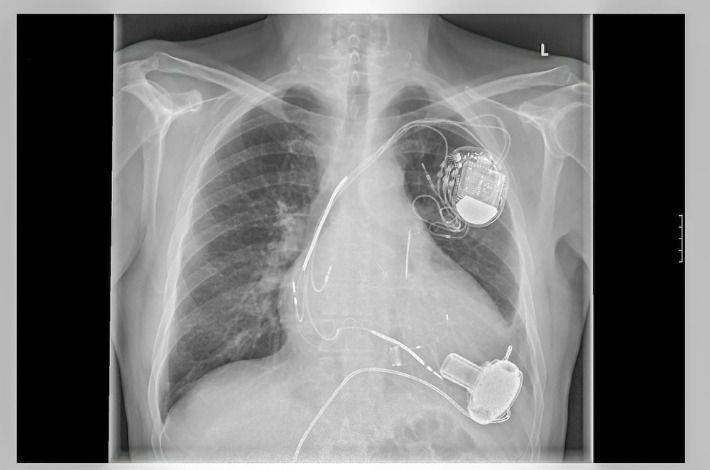

קוצב לב הוא מכשיר אלקטרוני שתפקידו לשלוח אותות חשמליים ללב בכדי לדאוג שיפעם בקצב סדיר. הלב מתפקד כמשאבה עשויה שריר, אשר נשלטת ע"י אותות חשמליים שמקורם בתאים מיוחדים בלב. הפרעה של אותות חשמליים אלו, מביאה לקצב לב איטי מדי או מהיר מדי, או לפעימות לא סדירות של קצב פעימות הלב, מה שמצריך השתלת קוצב לב חיצוני. השתלת קוצב לב היא תהליך פשוט יחסית: המחולל מושתל מתחת לעור ליד עצם הבריח בצד השמאלי של החזה. בדרך כלל המחולל מחובר ללב דרך כלי דם ראשי באמצעות סיב אלקטרוני גמיש .

ניתוח השתלת קוצב לב מבוצע בחדר צנתורים תחת הרדמה מקומית. חדר הצנתורים הוא חדר סטרילי המכיל את המכשור הנדרש לשם ביצוע הפעולה. מדובר בניתוח קטן יחסית, שבמהלכו מבוצע חתך באורך של מספר סנטימטרים, בדרך כלל באזור החזה הסמוך לכתף. לאחר ביצוע החתך, מוחדרת אלקטרודה או אלקטרודות, תלוי בסוג הקוצב המושתל, לתוך וריד הנמצא סמוך לאזור ההשתלה, ומשם ללב. על-מנת למצוא את המיקום המתאים לאלקטרודות, נעשה שימוש בין היתר במכשיר רנטגן הנמצא בחדר הצנתורים.